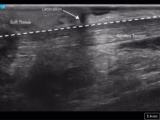

Measurement of systolic blood pressure using POCUS with color Doppler compared to with an intraarterial line

Henry Mayo-Malasky; Daniel Ying; Alekhya Bukkuri; Paul H. Mayo - This study compares the measurement of SBP using point of care ultrasound (POCUS) with color Doppler to the measurement of SBP using an intraarterial catheter